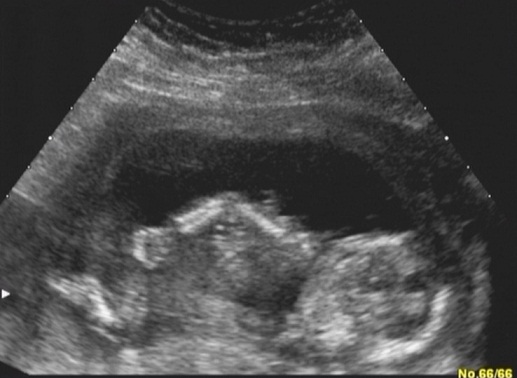

Hoztam én is képeket :P Profilból, ásítós, tappancsos na meg a bizonyíték, hogy kisfiú :wink:

Kép